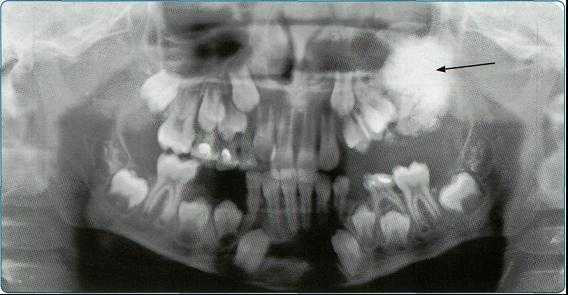

Особенно важно использовать ортопантомографию в детской стоматологии, где она не имеет конкурентов в связи с низкими дозами облучения и большим объемом получаемой информации. В детской практике ортопантомография помогает диагностировать переломы, опухоли, остеомиелит, кариес, периодонтиты, кисты, определять особенности прорезывания зубов и положение зачатков.